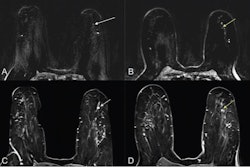

Moassefi and colleagues conducted a study that included 395 women with endometriosis that had been pathologically confirmed between 2015 and 2024. They also created an age-matched group of 356 individuals that underwent the same MRI protocol (that is, sagittal fat-saturated T1-weighted pre- and postcontrast and T2-weighted imaging) but were not diagnosed with the condition. Of the total study cohort, 12.5% were used for testing and validating the deep-learning algorithm (a 3D-DenseNet-121 classifier model). Seven abdominal radiologists experienced in endometriosis MR imaging and surgical planning and one women's imaging fellow with specific training in endometriosis MRI reviewed a selection of images and recorded any endometriosis detection results.

The deep-learning algorithm "demonstrated robust performance," the authors wrote: the most accurate predictions of endometriosis were achieved using T2-weighted and sagittal fat-saturated T1-weighted pre- and postcontrast images.